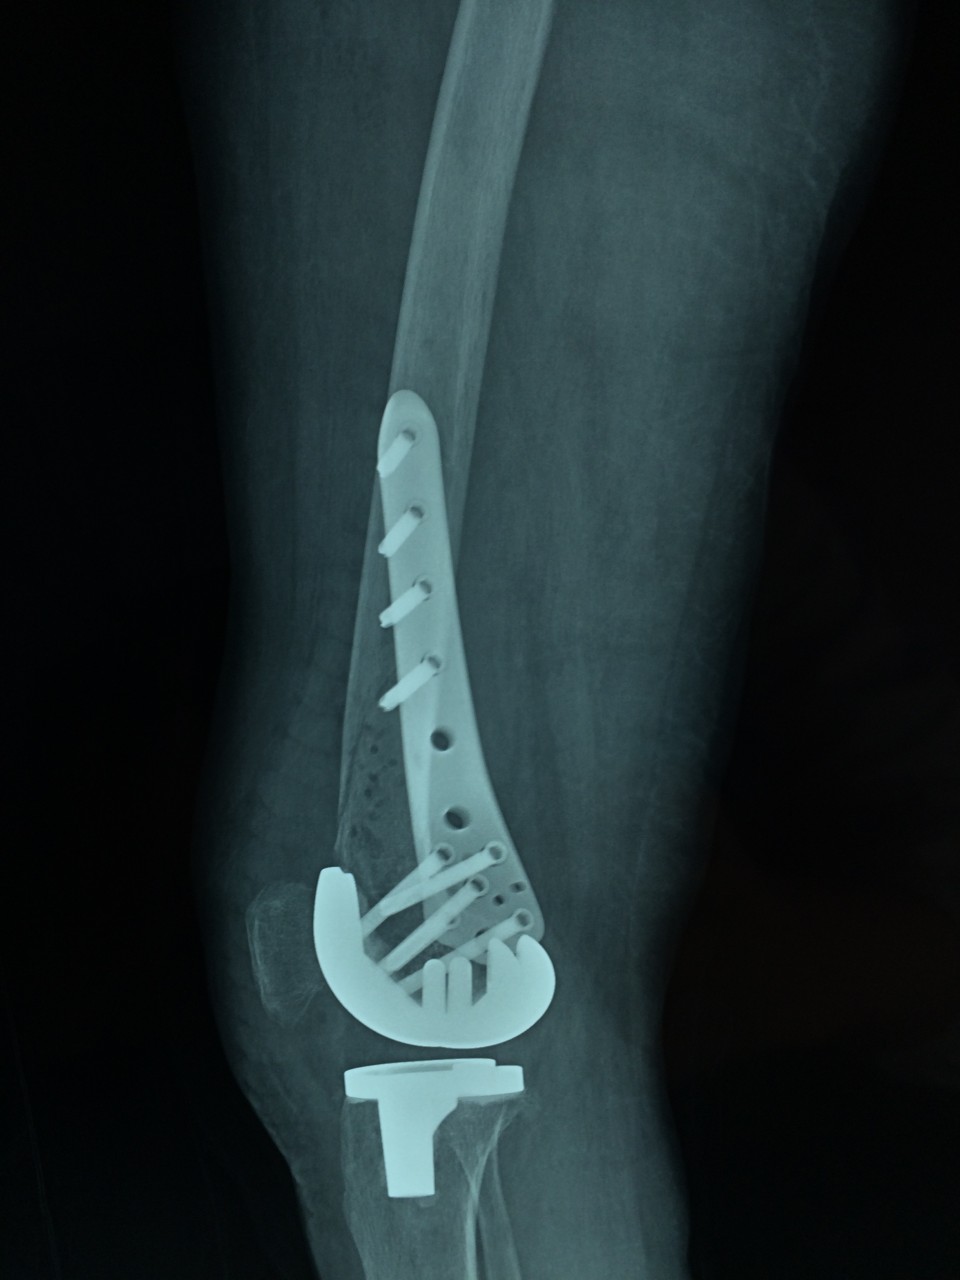

近日,我院关节中心成功完成一例重症类风关合并股骨远端骨折患者的关节置换手术。该患者长期服用激素及免疫抑制剂,骨质疏松较重;受伤前膝关节无法伸直,屈曲畸形,膝关节活动度仅15°;骨折的部位位于股骨远端,骨折处理不当,会直接影响假体的安置,造成手术的失败,因此手术难度非常大,对手术程序及逻辑性的严密度要求高。针对患者的复杂病情及手术难点,关节中心胡勇教授在风湿科、麻醉科的大力配合下,一期完成了骨折固定及人工表面全膝关节置换术。术后患者下肢力线恢复良好,骨折解剖复位,关节恢复过伸,术后5天,关节屈伸活动度恢复致40°。该手术的完成,标志着我院关节中心在复杂性关节病的治疗上又迈出了坚实的一步。